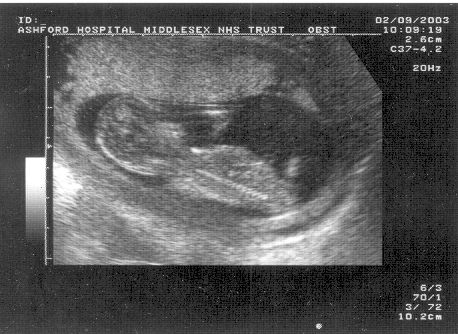

Yup, on 2nd september, Estelle

and Nick went to Ashford Hospital

for their 12 week scan,

expecting to later surprise everyone at work by bringing in an

ultrasound and announcing that we were going to be parents

again.

We weren't expecting quite such a surprise ourselves! TWINS!

Pics:

One baby: